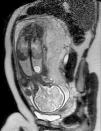

Embarazo controlado; en la ecografía de la semana 12 se detecta una imagen anecoica en el hemitórax izquierdo, que permanece sin cambios en controles posteriores. Se amplía estudio mediante resonancia magnética (RM) en la semana 30 + 4 de gestación (fig. 1), donde se establece como primera posibilidad diagnóstica el quiste broncogénico, planteando diagnóstico diferencial con otras malformaciones broncopulmonares, como el quiste de duplicación esofágico. Parto con fórceps en la semana 41 + 3, peso al nacer 4.150 g y Apgar 7/8; no precisó reanimación; parálisis braquial con fractura clavicular izquierda, sin otras incidencias en el periodo neonatal.